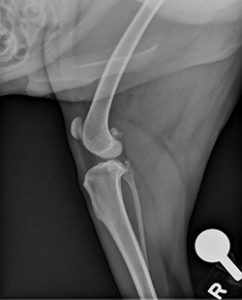

Diagnosing complete tears of the CCL is easily accomplished by a combination of observation of your pet’s gait, palpation of the knee and radiographs (X-rays). For early partial tears, however, it can be a bit more complicated and may sometimes require advanced imaging such as MRI or surgical exploration to physically look at the ligament. X-rays are usually taken to confirm the presence of joint effusion (fluid accumulation in the joint which indicates that there is a problem within the joint), the degree of arthritis, to aid in surgical planning and to rule out concurrent disease conditions such as bone cancer. For certain treatments, like tibial plateau leveling osteotomy (TPLO) and tibial tuberosity advancement (TTA), specific X-rays are required and your surgeon may need to repeat radiographs of the knee even if your veterinarian has already taken some. Specific palpation techniques that veterinarians use to confirm a problem with the CCL are the “cranial drawer test” and the “tibial thrust test.” These tests confirm abnormal motion in the knee and hence a rupture of the CCL. X-rays do not show the status (i.e. intact or damaged) of the CCL or the meniscus because those structures cannot be seen on X-rays. Therefore, it is crucial that the surgeon evaluate both of these structures (meniscus and the cruciate ligament) when performing the chosen surgical repair. This can be done either via an arthrotomy (opening of the joint) or with the use of a minimally-invasive camera (arthroscope) and is generally combined with the surgical procedure itself because both procedures require full anesthesia and clipping of the animal.

Tibial plateau leveling osteotomy (TPLO) involves making a circular cut in the tibial plateau and rotating the contact surface of this bone until it attains a relatively level orientation that puts it at approximately 90 degrees to the attachment of the quadriceps muscles (see Figure 2). This orientation of the tibial plateau renders the knee relatively stable, independent of the CCL. The cut in the bone needs to be stabilized by the use of a bridging bone plate and screws. Once the bone has healed, the bone plate and screws are not needed, but are seldom removed unless there is an associated problem. The greatest advantage of this technique is the perceived superior outcome (limb function and less progression of arthritis) compared to traditional suture techniques especially in young, large breed dogs. The major disadvantage is the need to perform an osteotomy. Any osteotomy requires healing of the bone and if a problem is observed (such as implant failure, failure of the bone to heal), it may require multiple revision surgeries and the outcome may be poor. Luckily, such complications are rare, especially when the procedure is performed by an experienced surgeon.